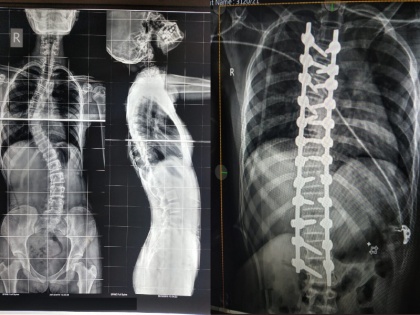

‘कायफोस्कोलिओसिस’ हा विकाराने त्रस्त केले शस्त्रक्रियेसाठी २४ स्क्रू वापरण्यात आले व तिची पाठ सरळ करण्यात पूर्णपणे यश आले.

शिरूर तालुक्यातील रामलिंग गावातील शेतकरी कुटूंबातील ही मुलगी आहे. मागील काही वर्षांपासून मुलीच्या पाठीला बाक होता. तिला ‘कायफोस्कोलिओसिस’ हा विकाराने त्रस्त केले होते. तिच्या पालकांनी अनेक खाजगी डॉक्टरांना दाखविले. पण शस्त्रक्रियेचा खर्च खुप असल्यामुळे पालक उपचार टाळत होते. ससून रुग्णालयामध्ये तपासणी केल्यानंतर त्यांना आशेचा किरण सापडला. रुग्णालायतील मणकाविकार तज्ज्ञ डॉ. अंबरीश माथेशूळ यांनी तिच्यावर शस्त्रक्रिया करण्याचा सल्ला दिला. त्यासाठी एक्सरे, एम.आर.आय., सिटीस्कॅन या तपासण्या करण्यात आल्या. मुलीच्या पाठीच्या ठिकाणी दोन बाक असल्याचे यामध्ये आढळून आले.

बाक सरळ करण्याची शस्त्रक्रिया नुकतीच यशस्वीपणे करण्यात आली. शस्त्रक्रियेसाठी २४ स्क्रू वापरण्यात आले व तिची पाठ सरळ करण्यात पूर्णपणे यश आले. शस्त्रक्रिये दरम्यान मज्जारज्जू व नसांना धक्का लागू नये व पायाची ताकद जाऊ नये यासाठी अत्याधुनिक नयूरोमॉनिटरिंग वापरण्यात आले. ही शस्त्रक्रिया तब्बल पाच तास चालली. त्यामुळे कमीतकमी रक्तस्त्राव व्हावा याची दक्षता घ्यावी लागली. शस्त्रक्रियेनंतर मुलीची पाठ सरळ झाली असून ती आता सर्वसामान्यांप्रमाणे आपले आयुष्य जगु शकणार आहे, अशी माहिती रुग्णालयाकडून देण्यात आली. रुग्णालयाचे अधिष्ठाता डॉ. अजय चंदनवाले यांच्या मार्गदर्शनाखाली डॉ. अंबरीश माथेशूळ, डॉ. सुशांत घुमरे, भूलतज्ज्ञ डॉ. सुरेखा शिंदे, डॉ. योगेश गवळी व डॉ. रोहित संचेती यांच्या पथकाने ही शस्त्रक्रिया केली.